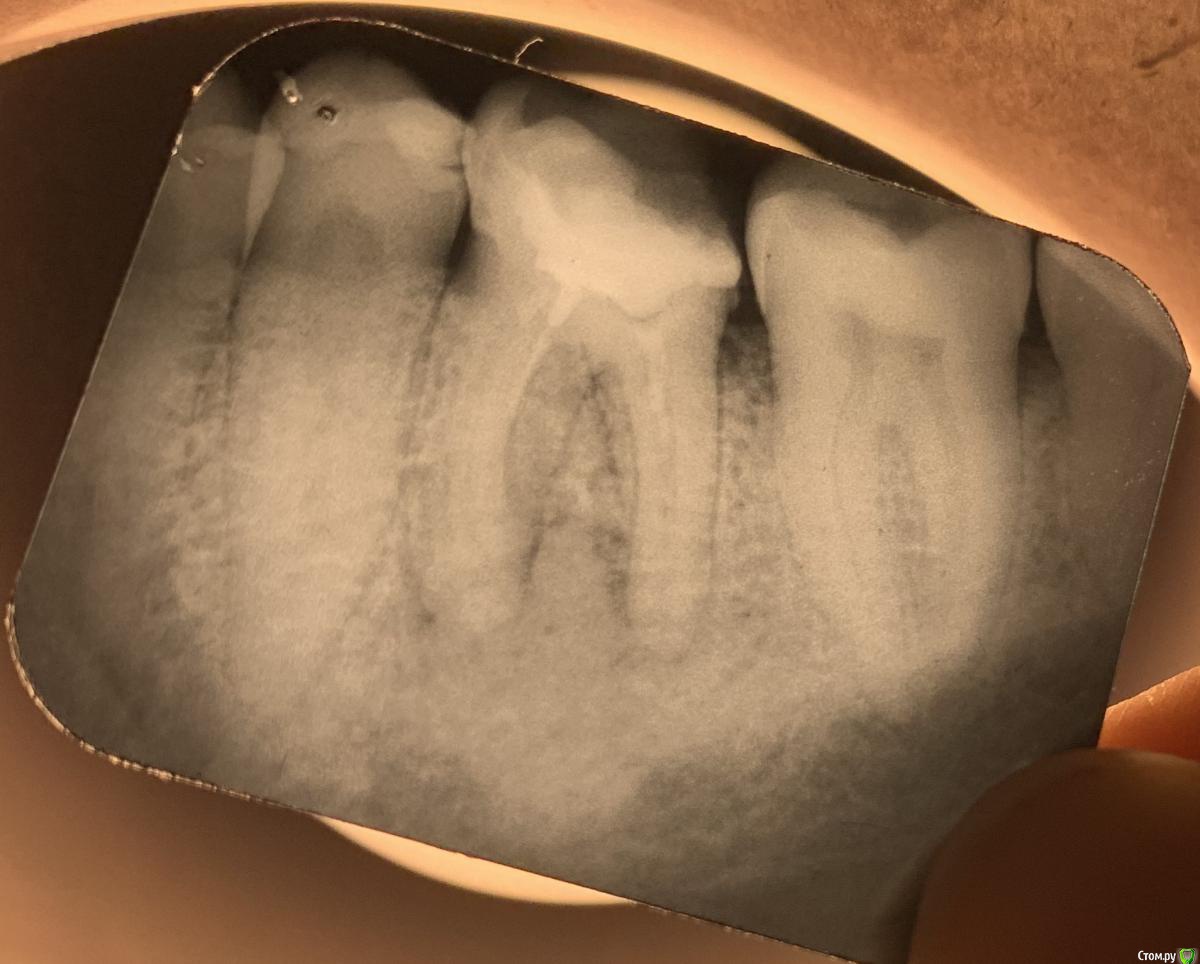

lodo4nik Опубликовано 7 июля, 2020 Поделиться Опубликовано 7 июля, 2020 Добрый день! Прошу помочь с решением судьбы зуба.На панорамном снимке мой стоматолог обнаружил новообразование в районе 36 зуба. Говорит причина в плохо залеченном канале-не вычистили все до конца при лечении.Этот зуб лечил около 10-15 лет назад (сейчас мне 35) в городской гос. поликлинике. Жалоб на него никаких нет и не было-не болит, не реагирует на холодное/горячее, выделений в районе зуба нет.Для уточнения сделали точечный рентген.Мой стоматолог советует зуб удалять и через пол года ставить имплант-т.к. будем сохранять зуб-сохраним новообразование. Сейчас это доброкачественное образование, которое со временем может перерасти в злокачественное. Во втором медцентре-хирург однозначно сказал удалять.В третьем медцентре сказали, что зуб можно спасти, но для уточнения отправили на КЛКТ. Посмотрели и сказали, что это киста и она уже очень разрослась-зуб под удаление, не спасти.Отправил снимки в четвертый медцентр, в столице (сам я живу в областном центре), знакомый посоветовал их-сказал что сохранили зуб, когда все остальные врачи настаивали на удалении. Оттуда пришел ответ-приезжайте, перепломбируем каналы, сохраним зуб. Но они КЛКТ не смотрели.Я в растеряности-что делать. Помогите окончательно определиться.И еще дополнительный вопрос. У меня повышен С реактивный белок высокочувствительный последние лет 8, не значительно, но постоянно 1.5-2.5 (референс <1) . Причина может быть в этом зубе?Ссылка на КЛКТ:https://yadi.sk/d/bVoEJ3dM53D3CAАрхив с КЛКТ:https://yadi.sk/d/YkVkCMyxDQsXQAФото без сжатия:https://yadi.sk/d/_LrW1Gt7YADgFQЗаранее спасибо! Ссылка на комментарий

red_butler Опубликовано 9 июля, 2020 Поделиться Опубликовано 9 июля, 2020 Я в растеряности-что делать. Помогите окончательно определиться. Здравствуйте, новообразования нет, это банальный периодонтит, для принятия решения нужно очно или по фотографии оценить оставшийся объем твердых тканей, если зуб возможно восстановить, то повторное лечение корневых каналов, если нет, то удаление 2 Ссылка на комментарий